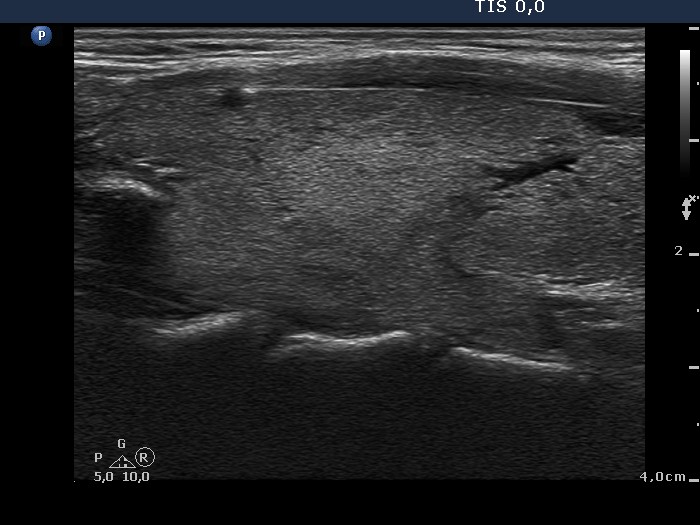

Graves' disease - Case 1049

Follow-up investigation 40 months after first visit (ultrasonographic picture 2)

Patient on daily 5 mg methimazole therapy in hypothyroid state

Right lobe, longitudinal scan.